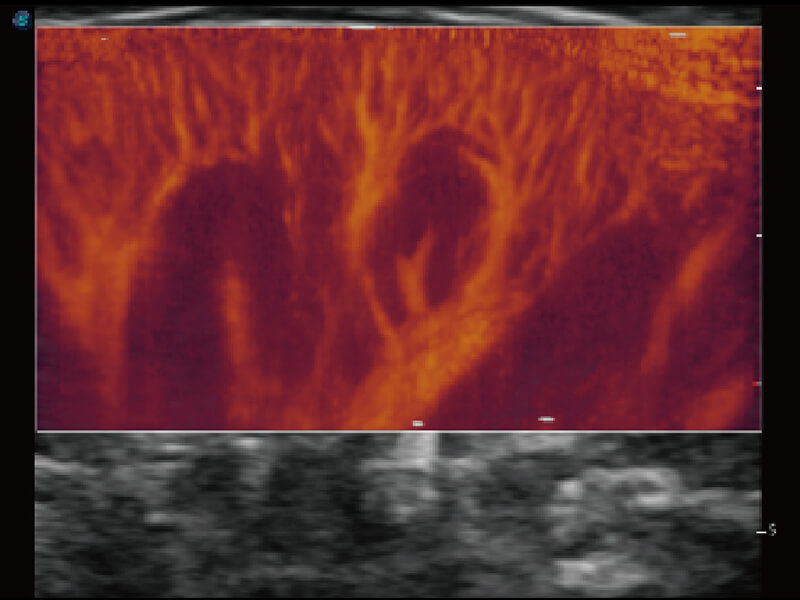

彩色多普勒超声诊断系统

S60探头工艺,从前端信号处理每一个环节采集无损声学数据,真实还原组织原貌,再现解剖细节。

超宽频带技术,为容积成像带来优质的二维图像基础,为您呈现丰富的结构细节,栩栩如生地展示宝宝的宫内形态以及各种组织的立体结构。